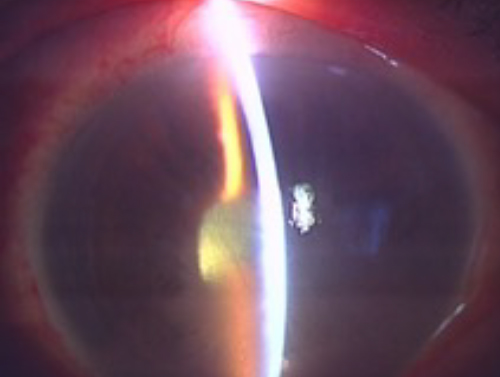

加齢性白内障

白内障には、この他にもアトピー性皮膚炎が原因となる「アトピー性白内障」、ぶどう膜炎など眼の炎症に続いて起こる「併発白内障」、生まれつきの「先天性白内障」など、いくつかの種類があります。

症状

水晶体の濁りが強くなると、かすみやまぶしさが増して視力が低下します。

白内障が原因で視力が低下すると、眼鏡をかけても見やすくはなりません。